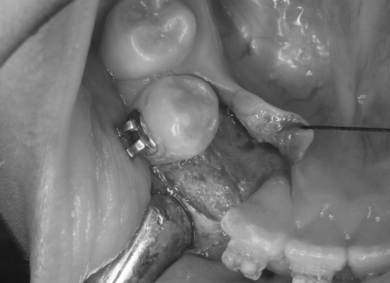

③ある程度の高さまで永久歯が萌出し、ブラケットがつけられるようになったらワイヤーをつなげ位置を調整する。

早期に外科的に介入したことで、通常のワイヤー矯正で正常歯列を獲得することができました。